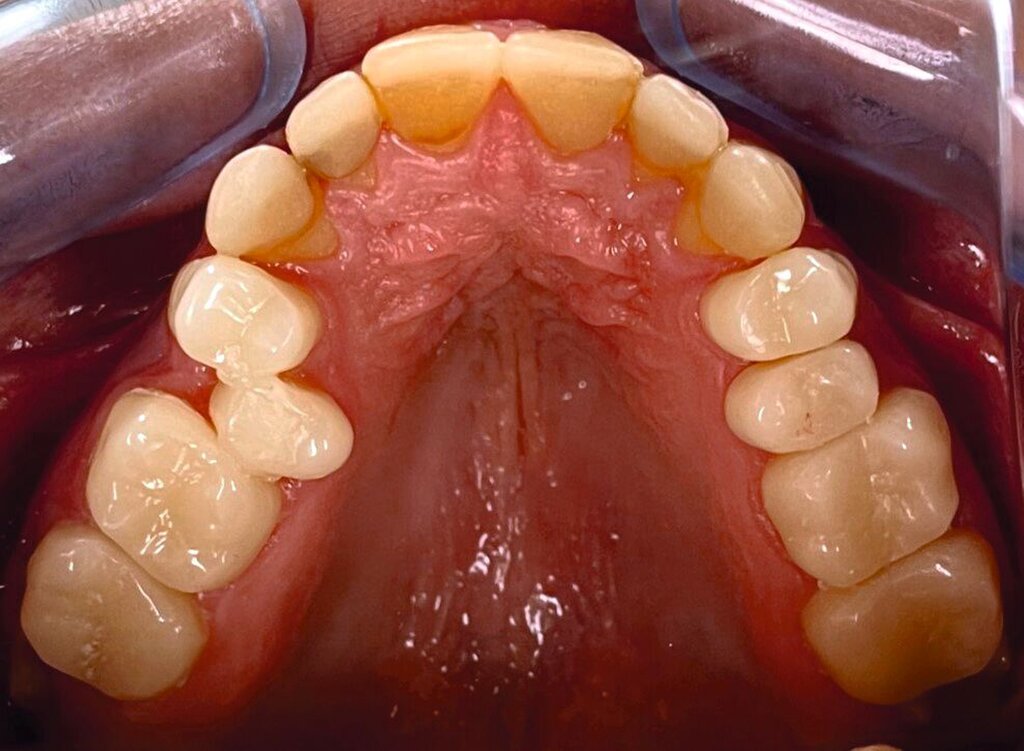

Die zu diesem Zeitpunkt seit fünf Jahren inserierten Frontzahnkronen zeigten Randverfärbungen sowie durch den Durchbruch entstandene Stufen zur natürlichen Zahnhartsubstanz (Abbildung 9). Diese wurden durch Sandstrahlen (CoJet, Solventum), anschließende Konditionierung mit einem Drei-Schritt-Etch-and-Rinse-System und Komposit (Filtek Supreme, Solventum; Tetric EvoFlow, Ivoclar Vivadent) korrigiert und abschließend poliert.